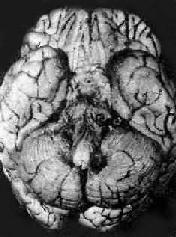

结核性脑膜炎

图18-14 结核性脑膜炎

脑基底部脑膜增厚,有散在的结核结节

病理变化以脑底最明显。在脑桥、脚间池、视神经交叉及大脑外侧裂等处之蛛网膜下腔内,有多量灰黄色混浊胶冻样渗出物积聚。偶见比粟粒还小的灰白色结核结节(图18-14)。脑室脉络丛及室管膜有时也可有结核结节形成。镜下,蛛网膜下腔内炎性渗出物主要由浆液、纤维素、巨噬细胞、淋巴细胞组成,常有干酪样坏死,偶见典型结核结节形成。病变严重者可累及脑皮质而引起脑膜脑炎。病程较长则可发生闭塞性血管内膜炎,从而可引起多发性脑软化。未经适当治疗致病程迁延的病例,由于蛛网膜下腔渗出物的机化而发生蛛网膜粘连,可使第四脑室上中孔和外侧孔堵塞,引起脑积水。